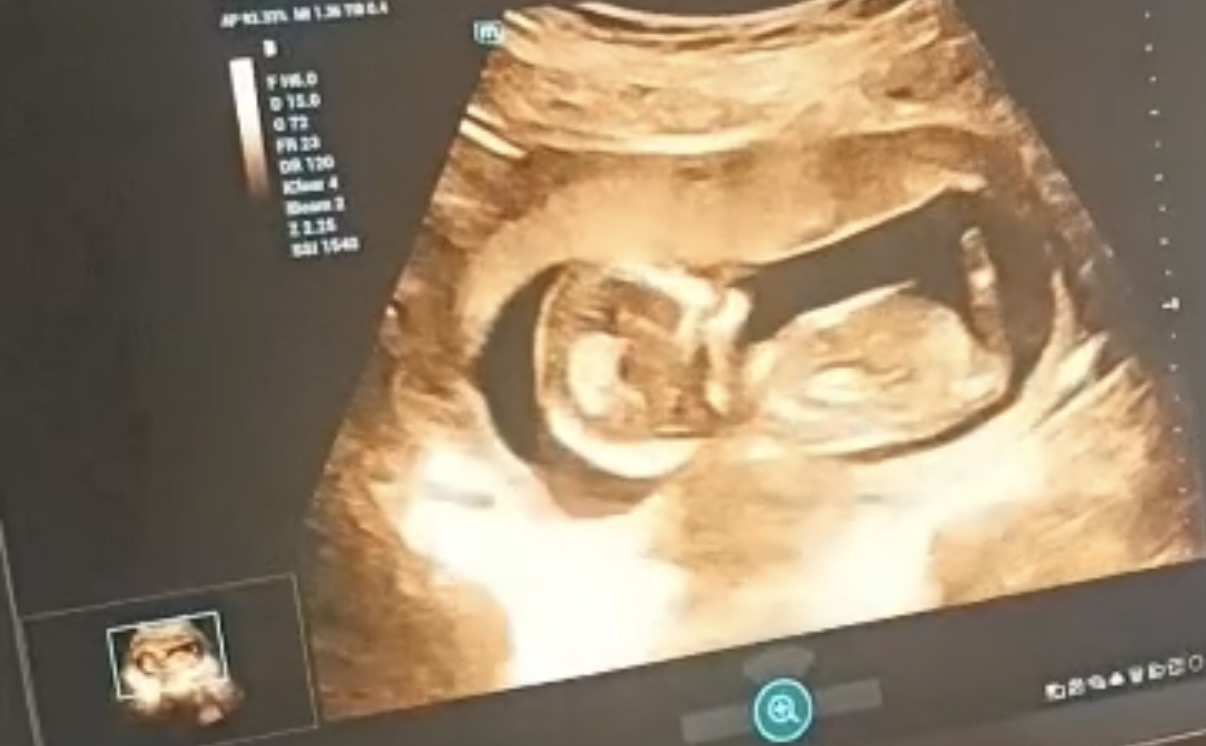

Ben hiç anlamıyorum canım ama nub teorisine göre bir kaç video izledim farklı açidan gözüken var mı

Canım video olarak var resim hiç yok bunuda o şekilde aldım bende hiç anlamıyorum